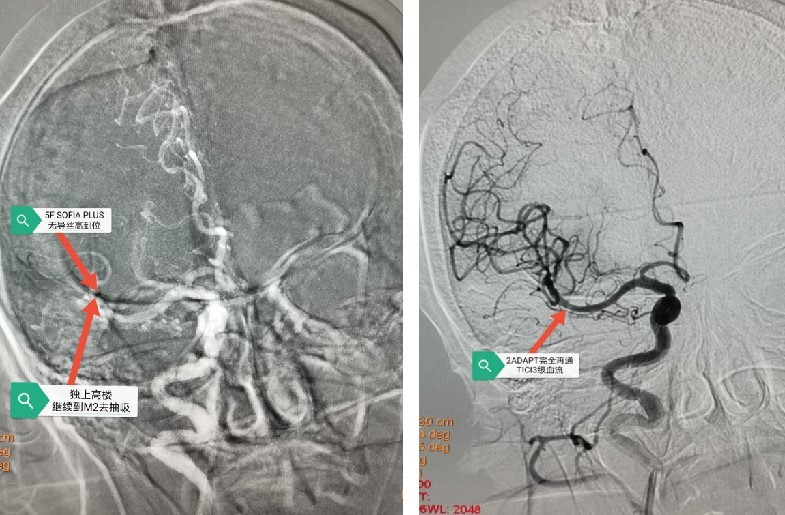

手术由张冬子执行院长带队、卒中中心李伟旺主任、陈斌副主任医师和杜乐乐住院总医师共同完成 。 造影显示“Ⅲ型弓” , 迂曲成角明显 , 交换技术无法将导管输送到位 。 危情时刻 , 脑组织濒临死亡 。 卒中团队讨论后 , 果断行颈动脉穿刺置鞘 , 之后行云流水般顺利将颅内血栓完全取出 , 快速恢复了颅内血流!术后30分钟患者肌力明显改善!之后使用专用血管封堵器完美封堵颈动脉穿刺点 。

第二次抽吸第二次抽吸后正位

取栓后血管成像示:右侧大脑中动脉完全再通